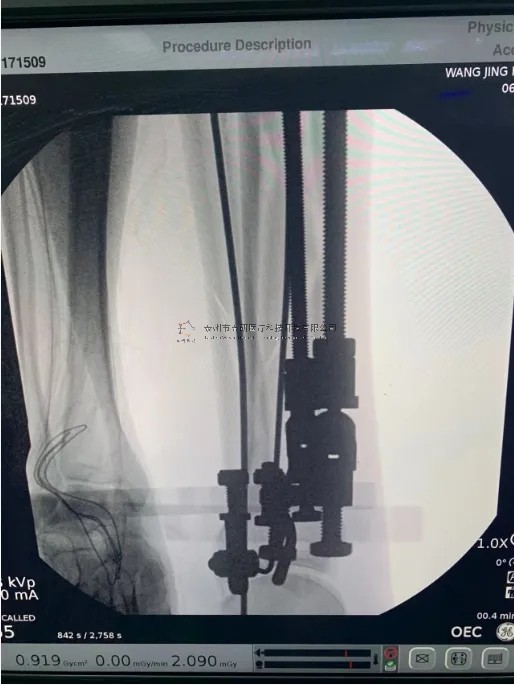

【手術(shù)資料】

10.webp.jpg

11.webp.jpg